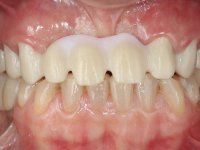

Female patient, 43 years old non-smoker. After a clinical and imaging examination, the patient presented teeth 1.7 / 1.4 / 1.3 / 2.2 / 2.3 / 2.4 / 2.6 with endodontic treatment in the upper jaw, showing absence of teeth 1.6 / 1.5 / 1.2 / 1.1 /2.1 and 2.5, and was rehabilitated with a 10-element monobloc metal-ceramic bridge. The anterior maxilla presented extensive vertical and vestibular bone reabsorption. In the lower jaw, two implants were placed at the site of teeth 4.6 and 4.5 rehabilitated with a metal-ceramic bridge. Teeth 3.6 and 3.7, with endodontic treatment, were rehabilitated with intra-radicular posts and a two-element metal-ceramic bridge. The antero-inferior teeth presented class III and IV resin restorations. Tooth 3.5 was absent. The patient had a vertical dimension of occlusion reduction, accompanied by accentuated dental wear and some ceramic fractures. Good oral hygiene.

In view of the clinical situation, oral rehabilitation was proposed to improve the aesthetic appearance, but also to solve the lack of posterior teeth, seeking a functional and aesthetic rehabilitation. The plan included replacing the metal-ceramic bridge by a bridge with Zr infrastructure coated with coronary and gingival ceramics. The edentulous area of the first quadrant would be rehabilitated with 2 implants and a bridge of two elements. It was intended with this treatment plan, to recover the vertical dimension of the occlusion and to reshape the dental anatomy, thus creating a more natural aesthetic appearance.

Alginate impressions were made at both arches arcades, accompanied by intermaxillary registration relations and collecting information with facial bow facial bow. In the laboratory, a provisional bridge with 13 elements in autopolymerizable acrylic was built, in which a metallic reinforcement was included. Teeth 1.7 / 1.4 / 1.3 / 2.2 / 2.3 / 2.4 and 2.6 were used as pillars. The metal-ceramic bridge was removed after performing longitudinal cuts with diamond burs. The dental abutments were reprepared and the temporary bridge was relined in the mouth with self-curing acrylic. After confection of the provisional bridge, a gingival epithesis was made using composite resin with gingival tonality in order to function as a mock-up, which allowed the patient to preview the possibility of using gingiva shade ceramics in the final work. This option was approved by the patient. Subsequently, the placement of two implants in the first quadrant was planned and executed. The provisional monoblock was removed for placement of the implants, and after surgery was again cemented provisionally. After the osseointegration period, the impressions were made to the maxilla. In the anterior zone, impregnated gingival retraction cords were used, and in the posterior areas, kaolin paste was used. Implant printing utilized the open tray technique. The printing material used was soft and regular putty addition silicone, both fast-setting. In the laboratory, the model of provisional restorations and the gingiva epithesis mock-up served as orientation for waxing the infrastructure. The plaster work model and the waxing of the infrastructure were placed in a laboratory scanner and yielded a digital work model, in which the scanning of the waxed infrastructure was superimposed. This overlay facilitated the CAD design of the Zr infrastructure. Subsequently, the CAD drawing for a CAM milling process provided the Zr pieces. The infrastructure was pigmented with a pinkish coloration, which favors the subsequent placement of gum shade ceramic. During the modeling of the infrastructure, the need to increase the occlusal wear on tooth 1.4 was detected. This was done in the real working model cast and an acrylic wear control guide was created, which accompanied the proof of the infrastructures. Corrective wear and Zr parts test were performed in mouth. During the test, the color choice of the gum shade ceramic was reassessed. The treatment was finished in the laboratory, and after approval by the patient, was definitively placed in the mouth.